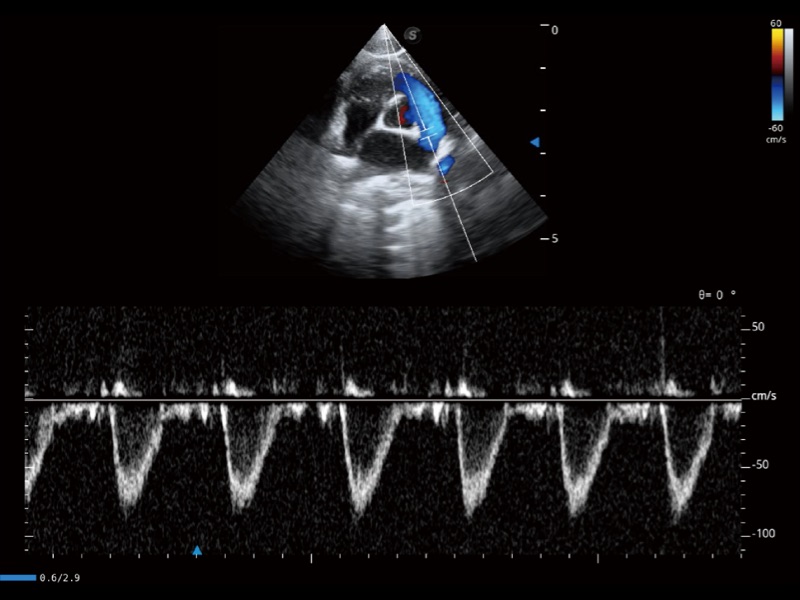

通过360度任意调节3条M型取样线,在同一心动周期上观察心脏不同位置的运动曲线,得到准确的心功能测量数据,有效评估心肌运动及左心室功能。

当心脏测量结果超出正常范围时,可实时预警提示动物医生,减少疾病漏诊概率。